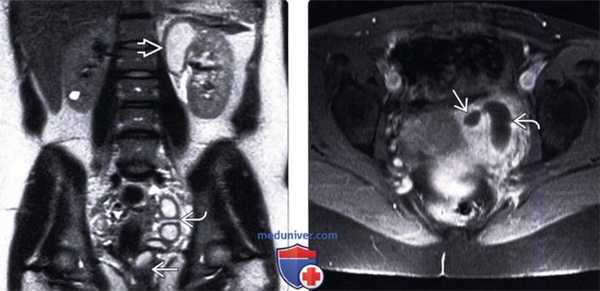

(Слева) МРТ, Т2-ВИ, корональный срез: удвоение левой собирательной системы с заметным гидронефрозом верхнего полюса и умеренным гидронефрозом нижнего полюса.

(Справа) МРТ, Т2-ВИ, корональный срез: у этого же пациента отмечается заметное расширение и извитость части эктопического мочеточника верхней лоханки.

(Слева) УЗИ левой почки в продольной плоскости: расширенный эктопический мочеточник, медиальнее и глубже по отношению к почке. Следует обратить внимание на кистозную дисплазию части верхнего полюса.

(Справа) Микционная цистоуретерограмма: определяется рефлюкс мочи в эктопический левый мочеточник, который открывается в уретру.